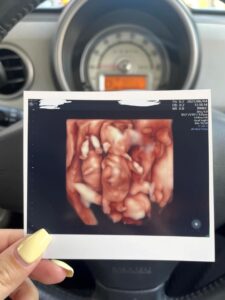

3人が写る唯一のエコー写真

三つ子ちゃんがお腹にいた頃のエコー写真と初めて撮った3ショット、そして現在の姿です。

3人が一緒に写ったエコー写真はたった1枚で“最初で最後”とのことでした。

三つ子ちゃんが一緒に写ったエコー写真を見たときにどう感じたかを尋ねると、ママさんは「信じられない気持ちと、本当に3人お腹の中にいるんだなと不思議な気持ちでした」と回答。